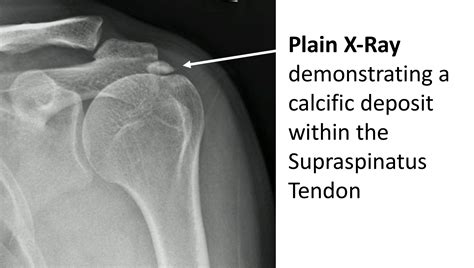

Diagnosing calcification tendonitis involves a combination of physical examination and imaging tests. The diagnostic process typically includes:

• Physical examination: A healthcare provider will assess the range of motion, strength, and tenderness in the affected area.

• Imaging tests: X-rays, ultrasound, or MRI scans can help visualize the calcium deposits and assess the extent of the damage.

Accurate diagnosis is crucial for developing an effective treatment plan tailored to the individual's needs.